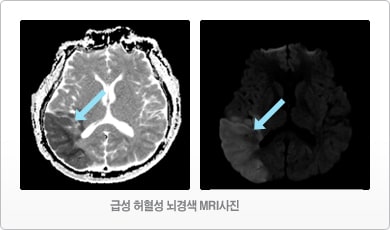

허혈성 뇌졸중 (뇌경색): 뇌 내부 혹은 뇌로 향하는 혈관이 막혀 특정 부위에 혈액 공급이 중단되는 상황을 말합니다.

- MRI 검사 : CT 검사보다 자세한 뇌의 병변과 혈관 상태를 진단받을 수 있습니다.